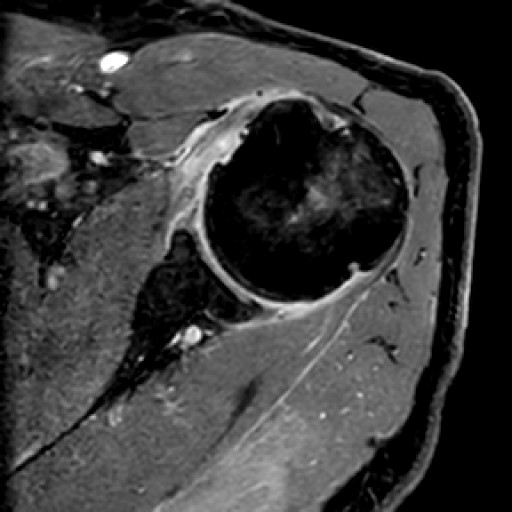

Zum wiederholten Mal war Dr. Georg Öttl als Vorsitzender in der Schultersession/obere Extremität eingeladen worden, in der Sportverletzungen und Überlastungen der Schulter diskutiert wurden.

Die Fachveranstaltung richtete sich an Radiologen in Klinik und Praxis mit einem besonderen Interesse an muskuloskelettaler Radiologie sowie speziell der Diagnostik von Sportverletzungen. Sie war aber auch für Orthopäden und Rehabilitationsspezialisten geeignet, die sich über aktuelle Möglichkeiten der bildgebenden Diagnostik bei Sportverletzungen und deren Einfluss auf die Therapieentscheidungen informieren wollten.